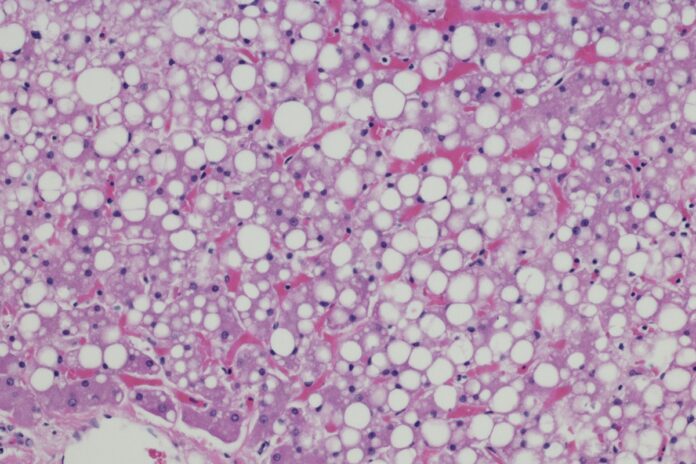

Cada vez mais comum entre os brasileiros, a esteatose hepática, conhecida popularmente como gordura no fígado, é uma condição muitas vezes silenciosa, mas que pode causar problemas sérios.

O quadro, que está relacionado à obesidade, sedentarismo e resistência à insulina, é caracterizado pelo acúmulo de células de gordura no tecido do fígado.